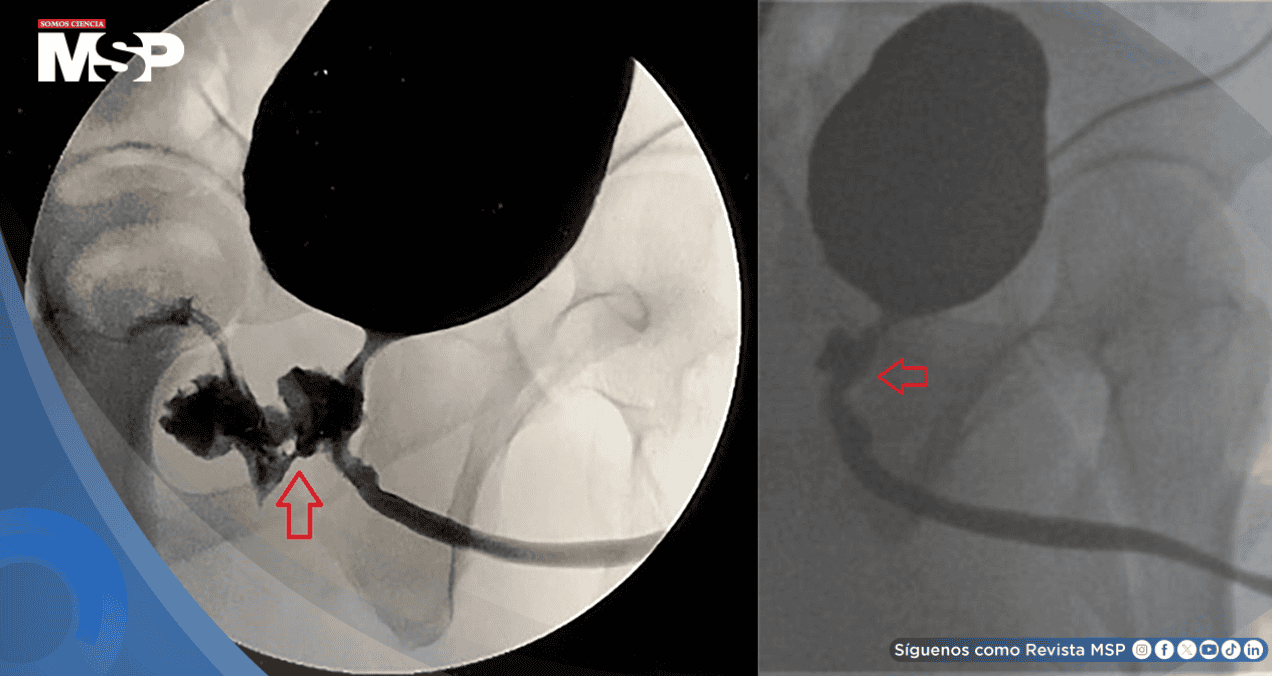

Los análisis de sangre mostraron signos de infección, al igual que un examen de orina. Para obtener una imagen más clara, se le realizó una tomografía computarizada de la pelvis, la cual reveló una infección en los testículos y, lo que es más importante, la presencia de una conexión anormal entre la próstata y el recto, lo que se conoce como fístula rectouretral.

Este pasaje, que permitía el intercambio de orina, heces y semen entre ambos órganos, tenía apariencia de ser un problema crónico.

Tras la recuperación, la sonda fue retirada y un estudio de imagen posterior confirmó que la fístula había desaparecido por completo. El paciente se recuperó satisfactoriamente, con una única secuela menor: un volumen de eyaculación ligeramente reducido, pero sin otros impedimentos.

Aunque existen diferentes métodos de imagen para diagnosticarla, la visualización directa mediante endoscopia suele ser clave. Respecto al tratamiento, si bien en contados casos seleccionados puede intentarse un manejo conservador, la gran mayoría de estas fístulas requieren una reparación quirúrgica para su solución definitiva, tal como se hizo en este caso.